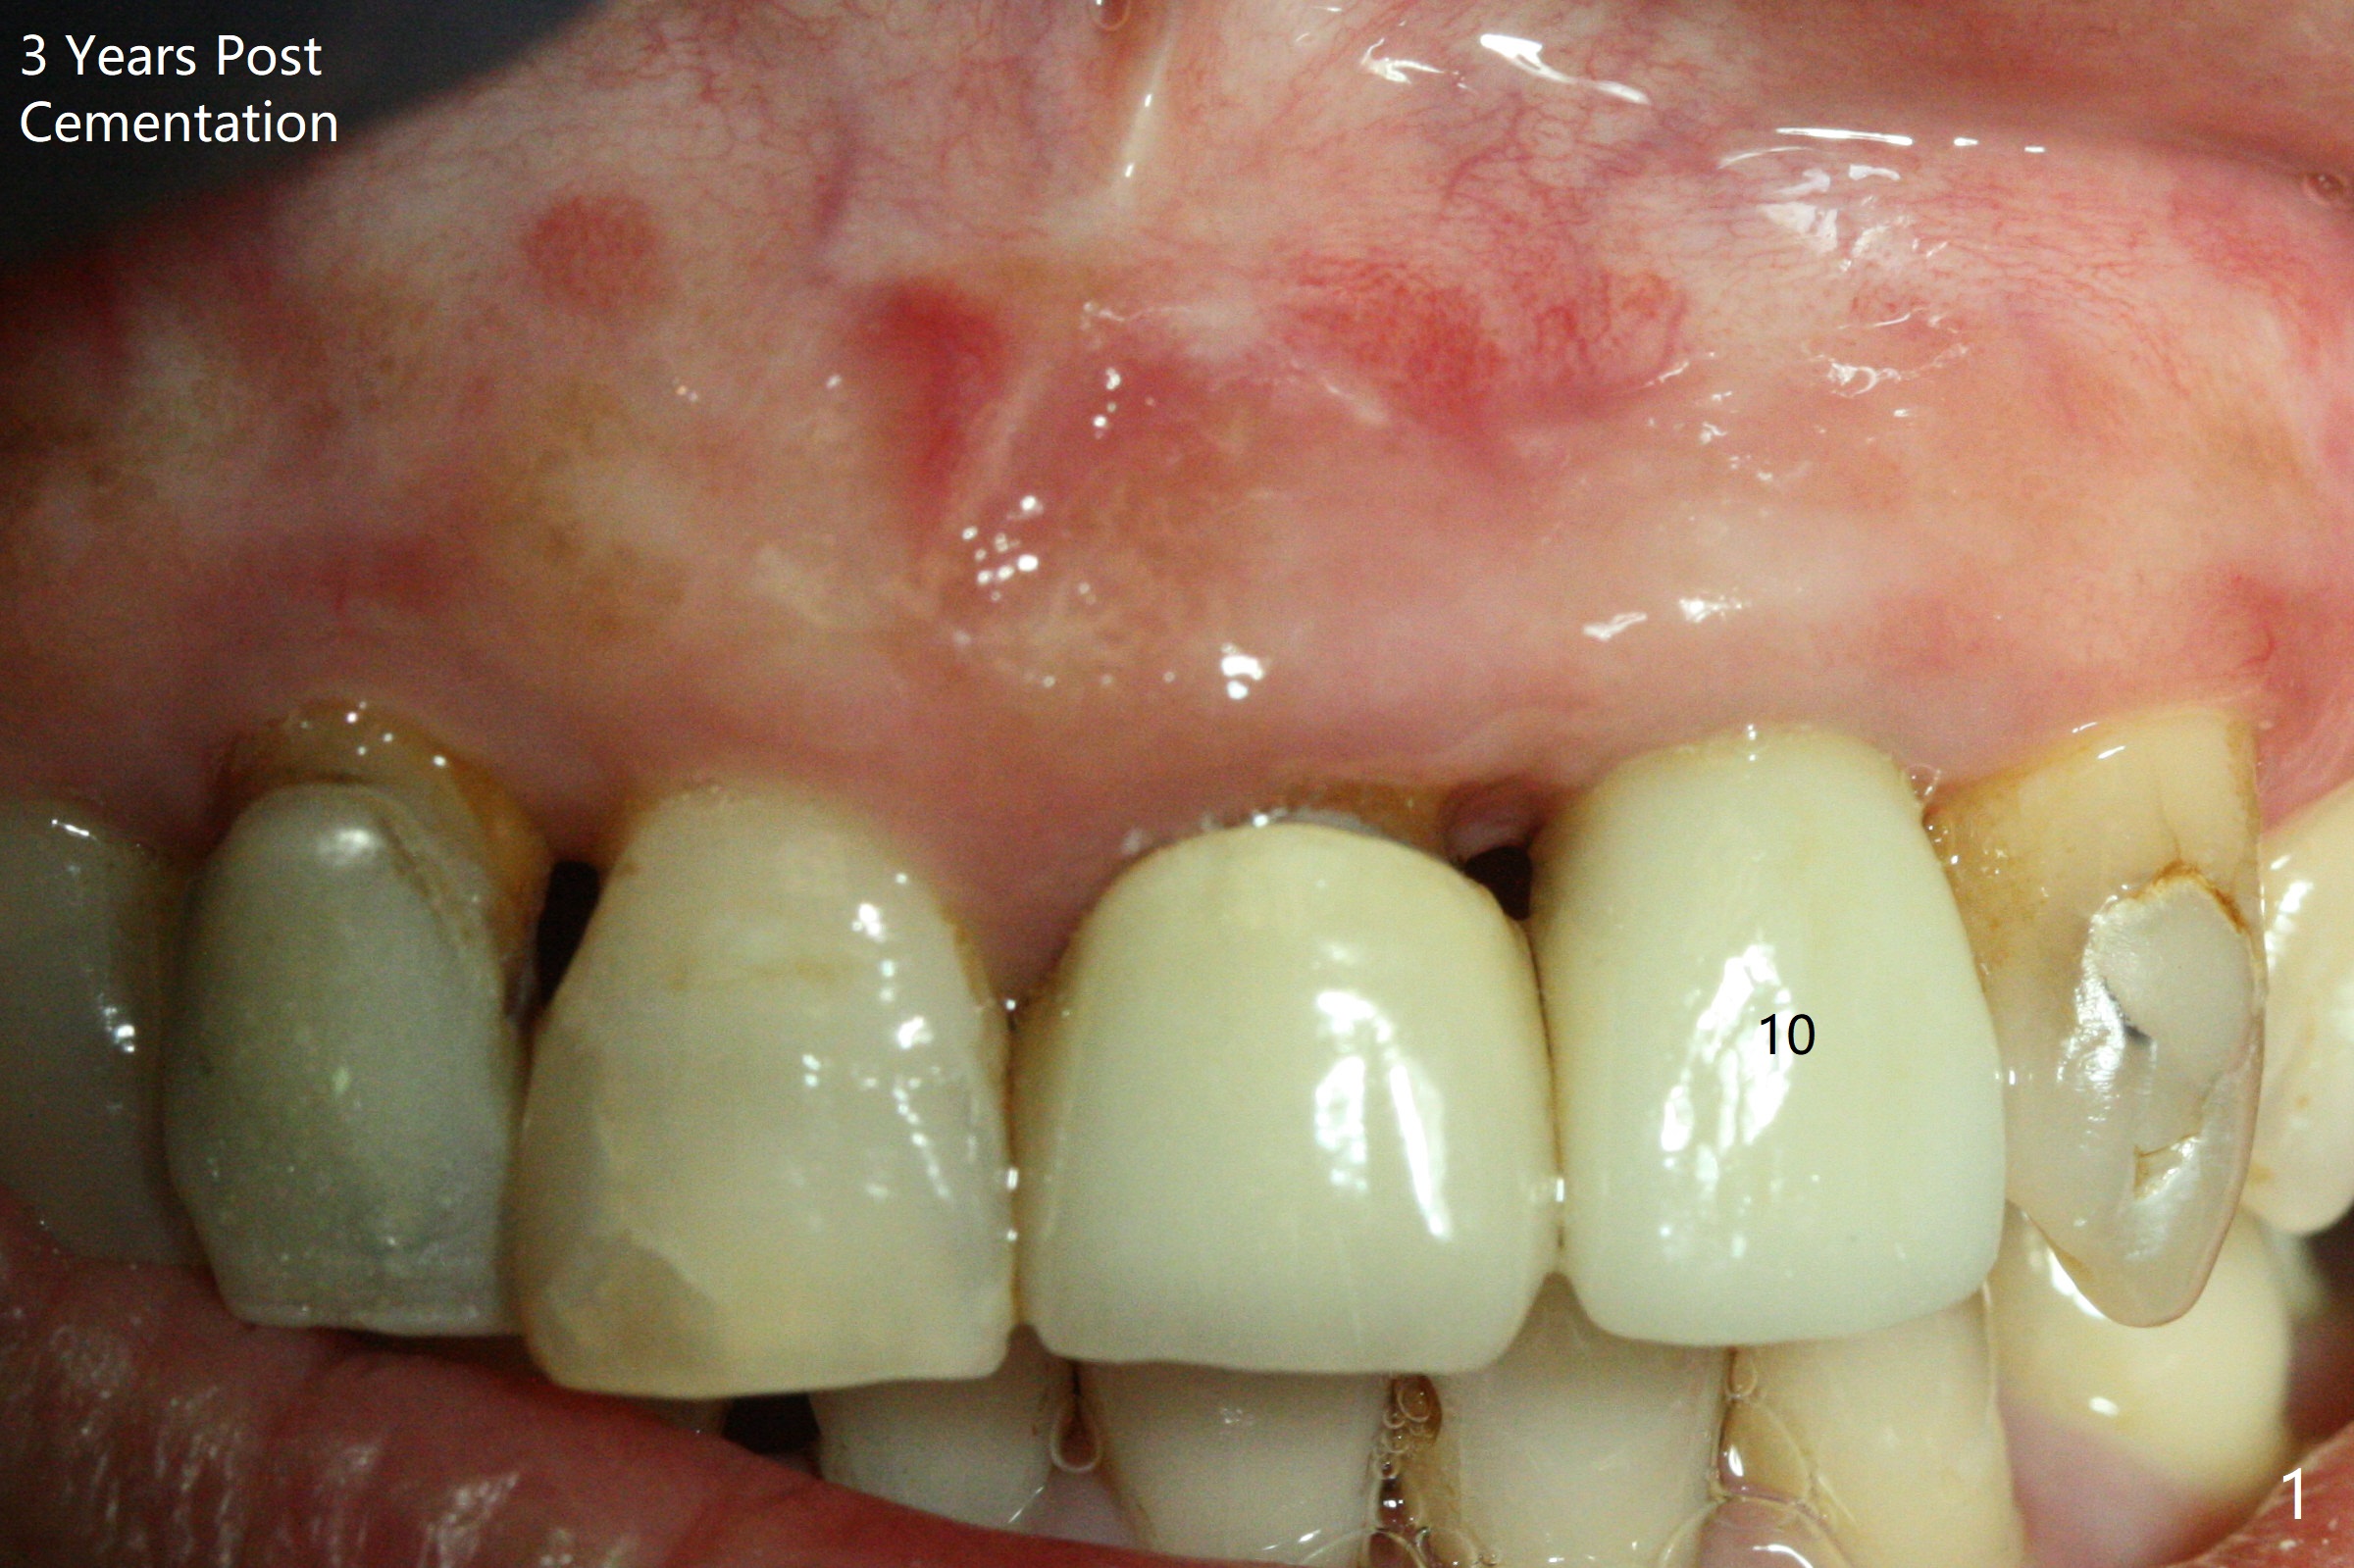

59岁女,口腔卫生差,害怕治疗,左上侧切牙即种牙冠粘固后6年4个月,同意深洗(图三)。虽然软硬组织没有特殊变化,再细点植体可能更好些(图一,二)。